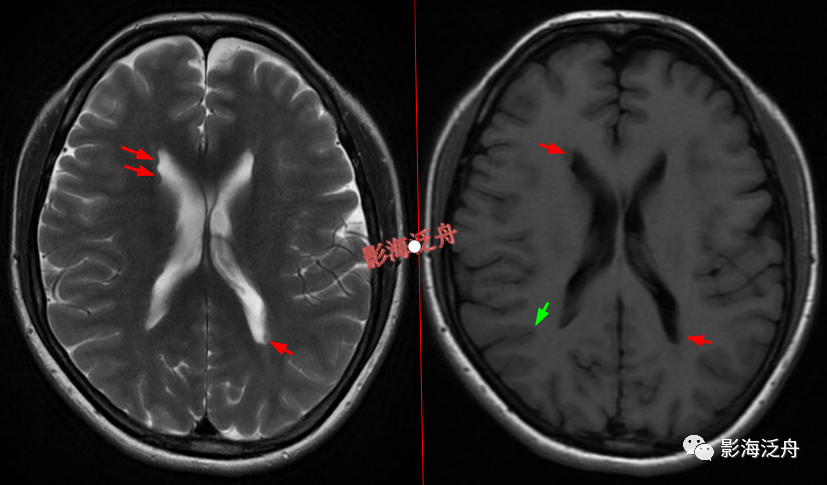

灰质移位,患者既往有癫痫病史。右侧侧脑室前角及左侧侧脑室后角可见异位的灰质结节(红箭),与大脑皮层下的灰质信号一致(绿箭),灰质异位患者多伴有癫痫症状。